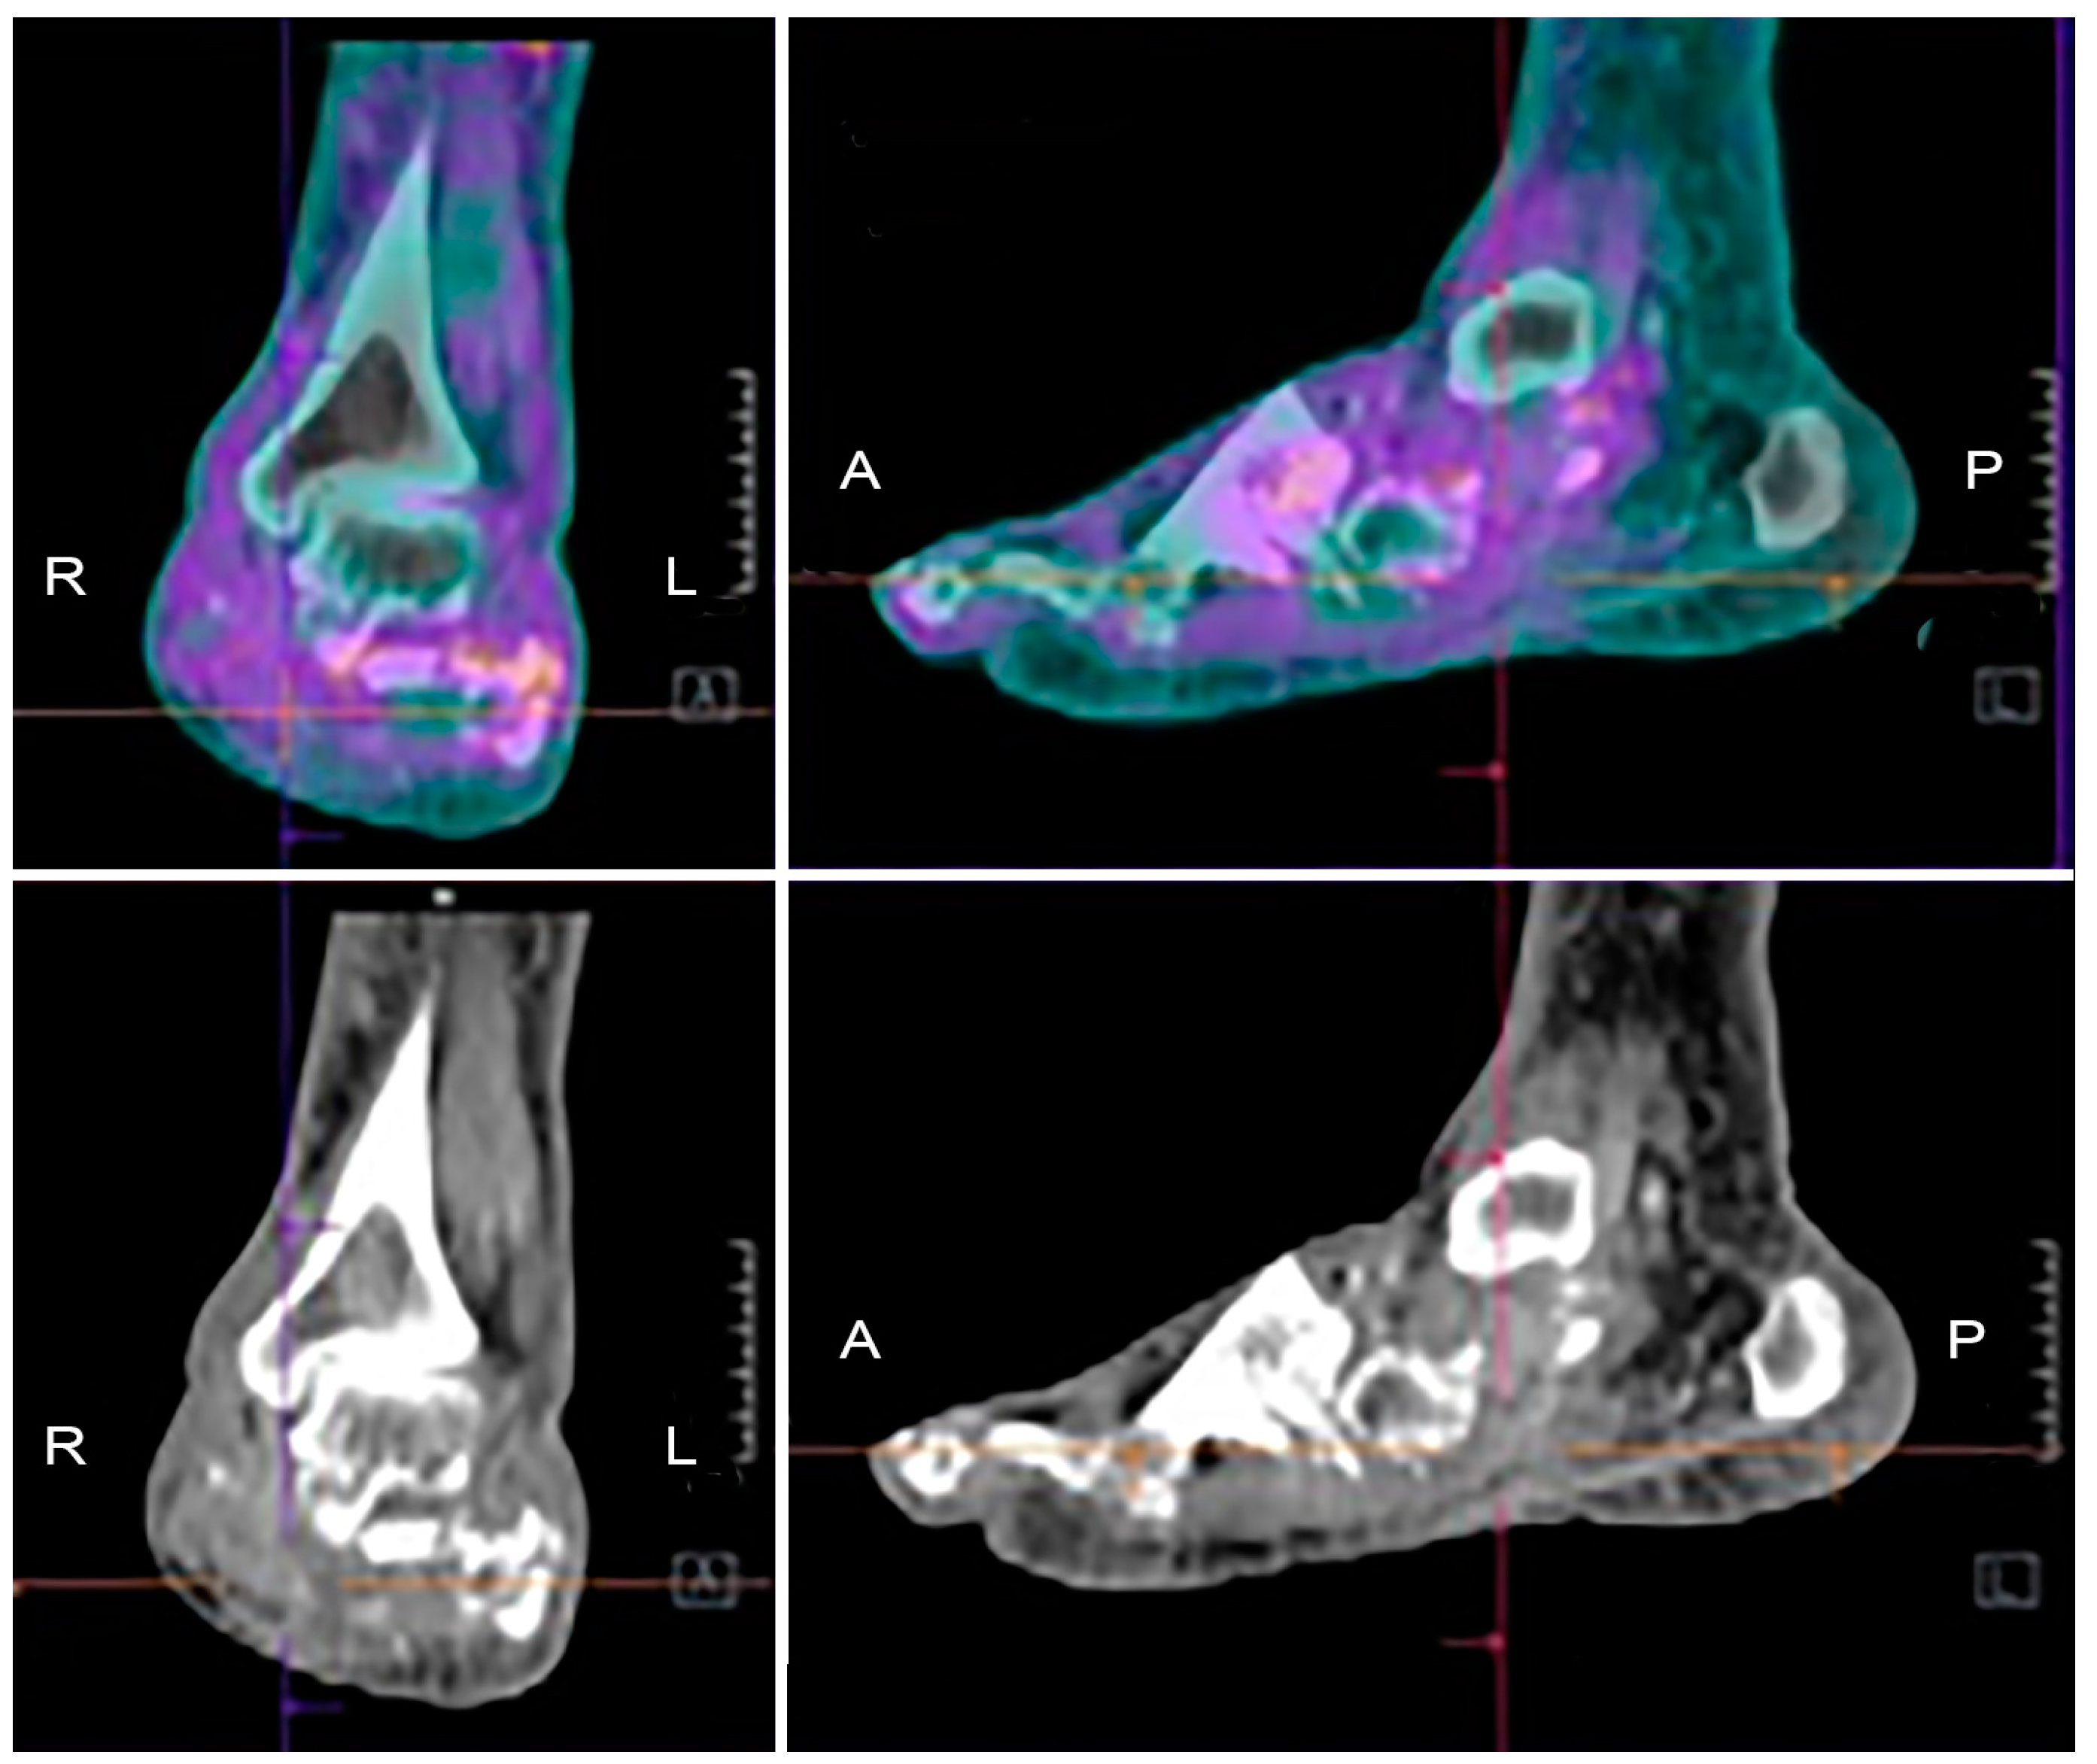

| [18F]FDG PET/CT | Focal or diffuse uptake clearly associated with bone at CT | Focal or diffuse uptake clearly associated with soft tissues at CT without bone involvement | Diffuse uptake involving tarsal/metatarsal joints and bone destruction at CT | Poor discrimination between infection and sterile inflammation. FP in Charcot and. after foot surgery |